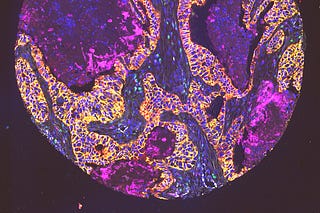

TARIO-2: A Whole-Transcriptome Foundation Model from H&E Alone

Spatial transcriptomics may be the richest measurement of a tumor we have. It's also almost never collected. Here's how we get around that.